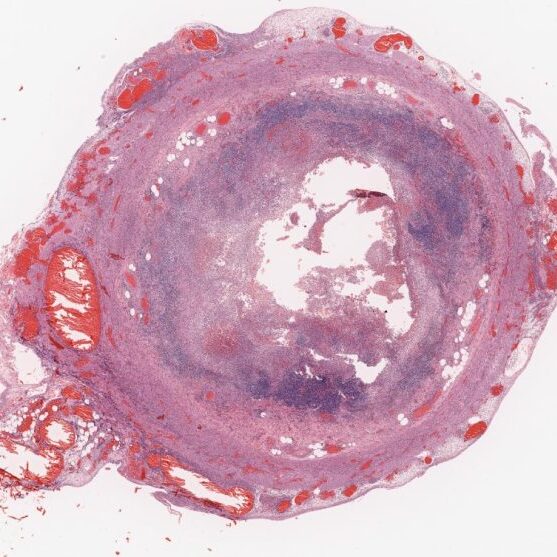

A virtual museum housing more than 1000 fully interactive, annotated virtual pathology specimens. View the clinical vignettes, talking pots and slides that accompany each specimen!

Use our Virtual Slide Viewer (like an online microscope) to view common and important conditions!